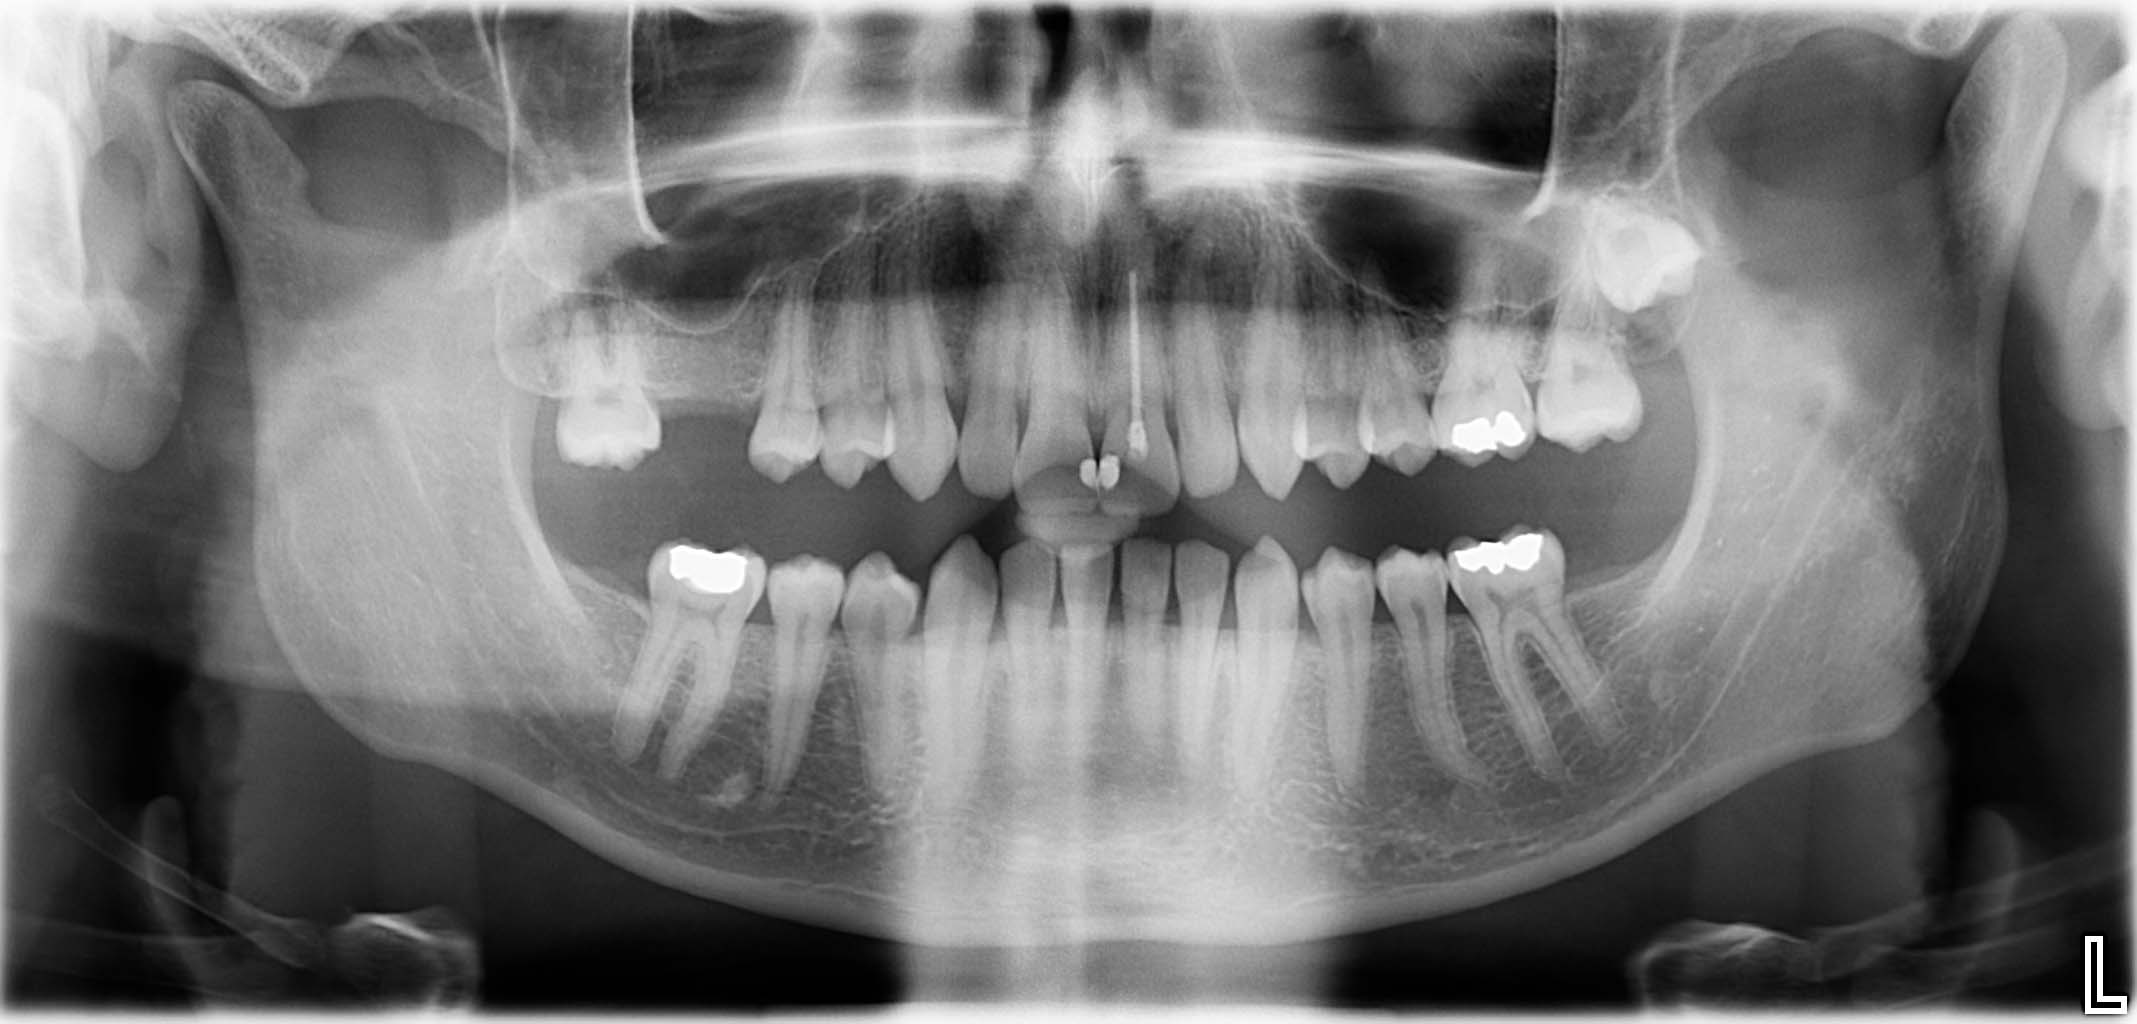

Erfolgreich implantierte Patientenfälle (klinische Fotos)